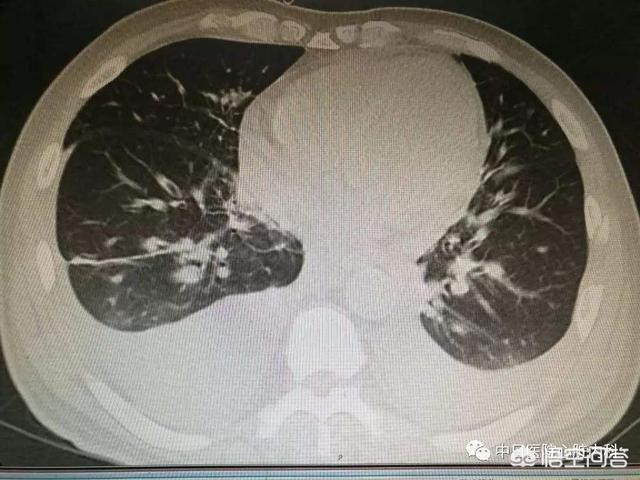

积水没了,胸膜增厚,积水还会反复吗?

视情况而定。目前不知道你是什么原因导致的胸腔积液。如果感染导致的话感恩控制好,不在感染的话,积水就不会反复